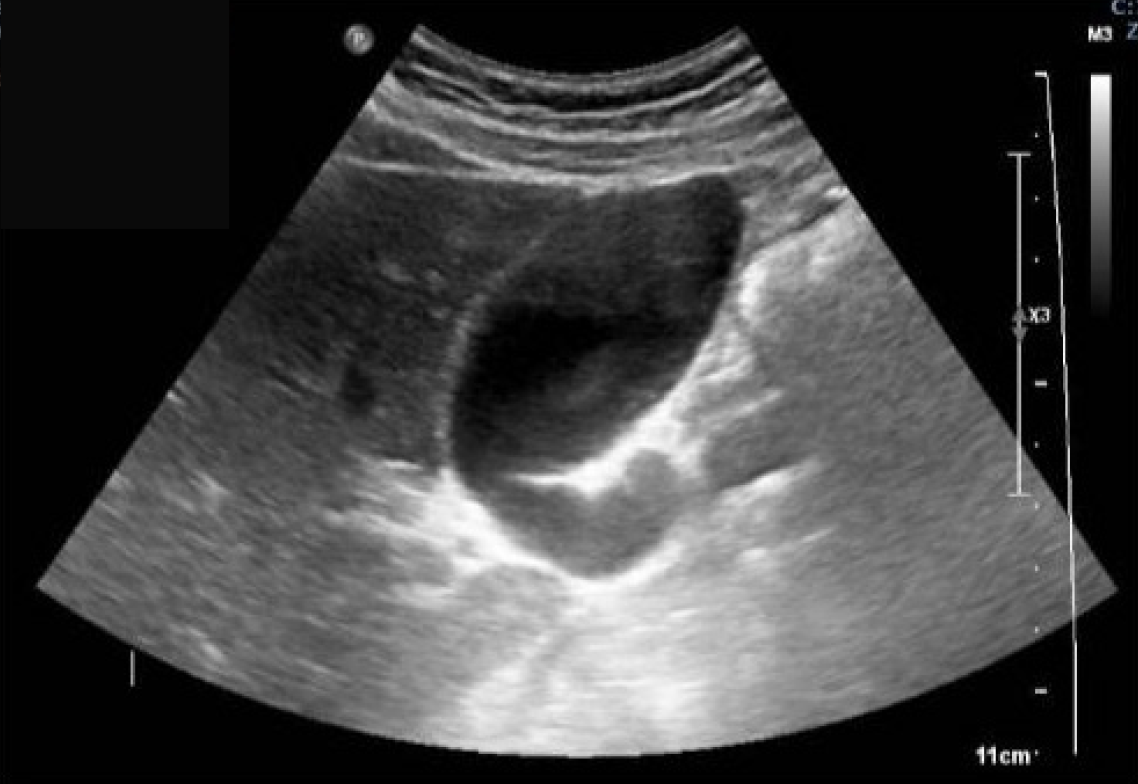

Figure 2 Abdominal ultrasound: Fluid-filled structure at the right iliac fossa.